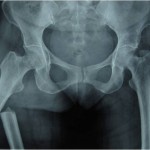

Introduction: The ischiogluteal bursa is an inconstant anatomical finding located between the ischial tuberosity and the gluteus maximus. Ischiogluteal bursitis is a rare disorder.

Case Report: We report the case of a 43-year-old female patient with bilateral calcifying ischiogluteal bursitis. The patient had no relevant medical history of systemic illness or major trauma to the buttock. After aspiration of both ischiogluteal bursitis which delivered calcareous deposits and instillation of a mixture of 1cc betamethasone (6 mg) and 4 cc of 1% lidocaine the patient was out of any complaints.

Conclusion: Calcifying ischiogluteal bursitis is a rare entity but easily diagnosed on radiographs. Aspiration and local steroid instillation give good relief from symptoms.